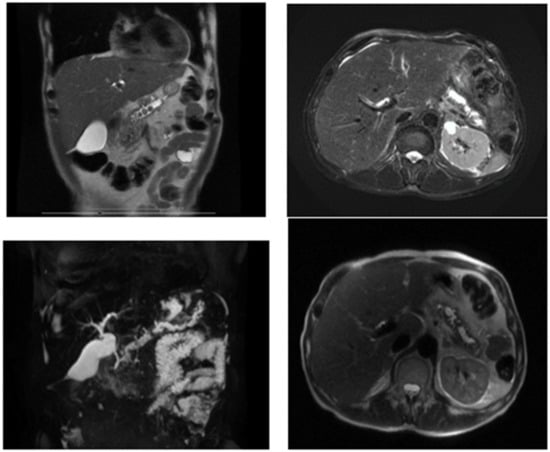

- Magnetic resonance cholangiopancreatography (Cholangio-MR): Destructuralized, inhomogeneous pancreas with fine inflammatory changes at the cephalopancreatic level; retrograde dilation of the Wirsung canal up to 15 mm above the isthmic segment with inhomogeneous content, and several stones of 1 cm diameter with obstructive pattern. Without dilatation of intrahepatic bile ducts. No hypo/hyperabsorbing areas suggestive of malignancy (Figure 2).